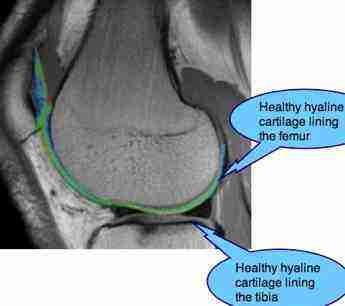

The ends of the weight bearing bones of the knee, the femur and tibia are

lined with a shiny, hard and super-slippery hyaline cartilage surface; it's not to be confused with the meniscus located inside the

joint. Look at a chicken drumstick to see what it looks like.